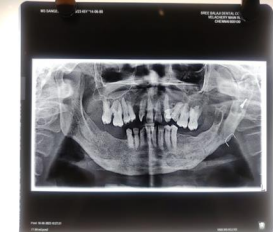

A patient reported to the OPD of Department of Oral and Maxillofacial surgery at Sree Balaji Dental College and Hospital, Chennai. The patient had a previous history of OKC operated back in 2012. She was also a known diabetic and was under medications for thyroid for the past 5 years. On examination there was a extra oral fistula with purulent pus discharge and multi-locular radiolucency in the subcondylar and condylar region indicating recurrent OKC and infection of the plate. Routine blood investigations were done and fitness was obtained under ASA 3. Keeping in mind the systemic co-morbidities, a hemi-mandibulectomy followed by a custom partial joint prosthesis was planned. The custom prosthesis was planned to restore the facial symmetry and functionality using 3 implant abutments for future dental rehabilitation. The patient recovery took about 1 week and passive mouth excercises began on the 5th day of the surgery. After 1 month of surgery the active mouth opening was found to be  33 mm which is almost satisfactory.

Figure 1